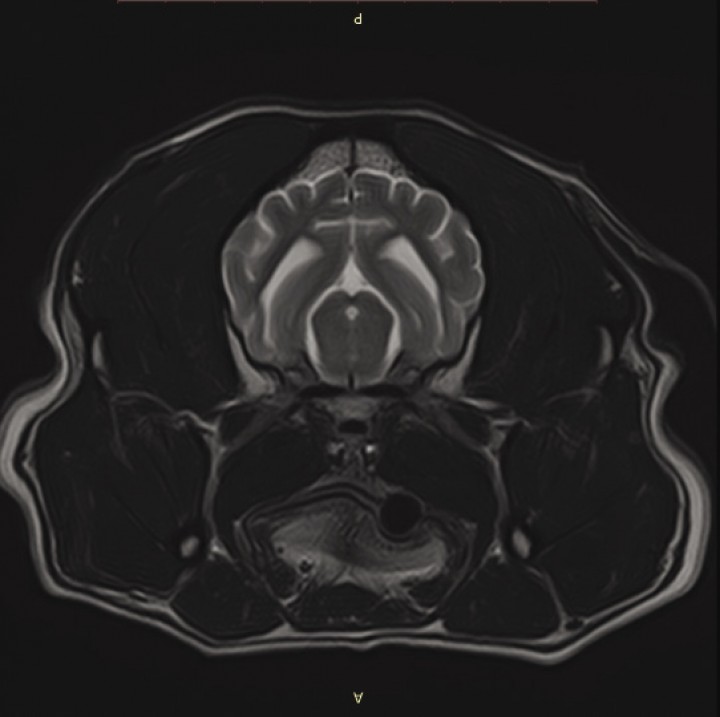

El examen físico y neurológico eran normales. Se estableció un diagnóstico diferencial principal de EMP o epilepsia estructural (neoplasia intracraneal – glioma, meningioma o metastática –, lesión vascular, proceso inflamatorio-infeccioso). Se realizaron las siguientes pruebas complementarias: hemograma, bioquímica y resonancia magnética craneal (Vantage Elan, Canon Medical Systems, 1,5 T, Nasushiobara) obteniendo imágenes en planos dorsales, transversales y sagitales y secuencias ponderadas en T1, T2, FLAIR y T1 poscontraste. La RM evidenció una dilatación ventricular leve (que teniendo en cuenta la raza se consideró una variación anatómica) y un ligero incremento del patrón de surcos y circunvoluciones cerebrales, compatible con una atrofia cerebrocortical leve, que fue considerado normal para la edad del paciente (Fig. 1). Se realizó por tanto un diagnóstico presuntivo de epilepsia mioclónica progresiva. Se instauró un tratamiento con levetiracetam (Keppra, UCB PHARMA SA, Bruselas) a 20 mg/kg cada 8 horas.

<p>Imagen de encéfalo mediante RM del caso 2. Secuencia ponderada en T2, en plano transversal. Se aprecia una leve dilatación de los ventrículos laterales y un ligero incremento del patrón de surcos y circunvoluciones cerebrales.</p>

Figura 1

Imagen de encéfalo mediante RM del caso 2. Secuencia ponderada en T2, en plano transversal. Se aprecia una leve dilatación de los ventrículos laterales y un ligero incremento del patrón de surcos y circunvoluciones cerebrales.

El diagnóstico de la enfermedad de Lafora se puede realizar mediante análisis genético o histopatología. El análisis genético está disponible para Teckels Miniatura de pelo duro, Beagles y Basset hounds.[ Swain L, Key G, Tauro A, et al. Lafora disease in miniature wirehaired Dachshunds. PLoS One. 2017; 2:12. [PubMed] , Hajek I, Kettner F, Simerdova V, et al. NHLRC1 repeat expansion in two beagles with Lafora disease. J Small Anim Pract. 2016;57(11):650-652. [PubMed] , Edwin J, Susan N. Expanded repeat in canine epilepsy. Science. 2005;(January):92093-92093. [PubMed] ] En nuestros casos, al no estar identificada la mutación en esta raza no se realizó ningún test genético. En algunos casos pueden hallarse cuerpos de Lafora en tejidos como el músculo estriado, el músculo liso de la vejiga urinaria o las glándulas apocrinas y ecrinas cutáneas, aunque su ausencia en estos tejidos no descarta su presencia en el encéfalo.[ Chambers JK, Thongtharb A, Shiga T, et al. Accumulation of laforin and other related proteins in canine Lafora disease with EPM2B repeat expansion. Vet Pathol. 2018. [PubMed] ] Mediante resonancia magnética craneal puede detectarse atrofia cerebrocortical y dilatación ventricular en algunos casos, aunque estas alteraciones no son específicas de la enfermedad de Lafora.[ Swain L, Key G, Tauro A, et al. Lafora disease in miniature wirehaired Dachshunds. PLoS One. 2017; 2:12. [PubMed] ] En uno de nuestros casos la RM mostró una ligera dilatación ventricular y una aparente atrofia cerebrocortical leve, aunque no es posible discernir si dichos cambios están relacionados con la epilepsia mioclónica o representan variaciones neuroanatómicas relacionadas con la raza y la edad del paciente. Sin embargo, la ausencia de lesiones evidentes en la resonancia magnética permitió en ambos casos descartar lesiones estructurales como causa de la epilepsia y establecer un diagnóstico presuntivo de EMP.